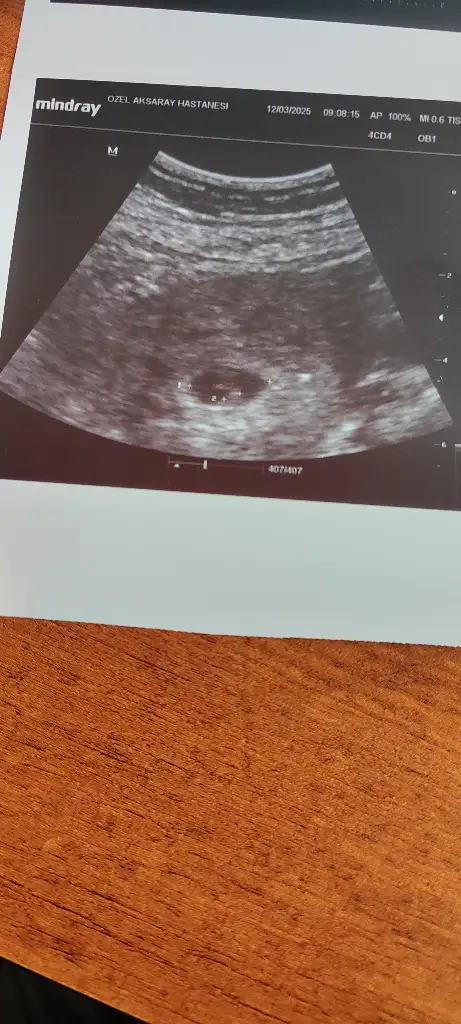

6 haftalik karından ultrasyon tahminde bulunabilir misiniz

5 ve 14. haftaya kadar olan ultrason fotolarınızı paylaşın. Vajinadan mı yoksa karından mı çekildiğini ve kaç haftalık olduğunu da mutlaka belirtin.:anneadayı: